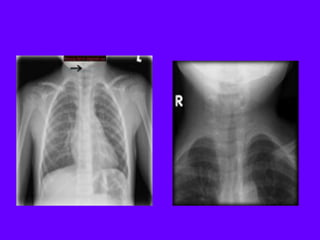

Steeple sign

The steeple sign (also called wine bottle

sign) refers to tapering of the

upper trachea on a frontal chest

radiograph reminiscent of a church

steeple. The appearance is suggestive

of croup, which should be obvious

clinically. A corresponding lateral x-ray

would show narrowing of the subglottic

trachea and ballooning of the

hypopharyn